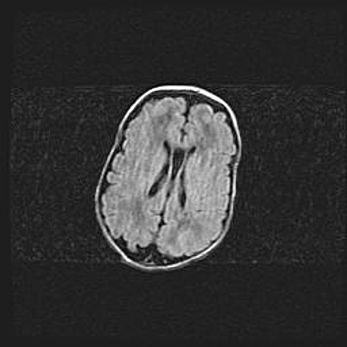

Открытая гидроцефалия.

Возраст: 9 месяцев 12 дней

Вес: 6800 г

Пол: мужской

Окружность головы: 41,5 см

Срок гестации: 28 недель

Гидроцефалия головного мозга у новорожденных имеет характерный признак: опережающий рост окружности головы приводит к визуально хорошо определяемой гидроцефальной форме сильно увеличенного в объёме черепа. Детские неврологи определяют следующие симптомы гидроцефалии у грудничков: выбухающий напряжённый родничок, частое запрокидывание головы, смещение глазных яблок к низу.